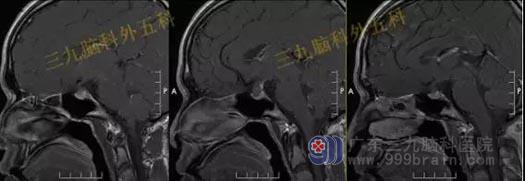

头部MR检查提示:鞍区短T1稍短T2异常信号影,大小约8mm×10mm×10mm,垂体受压下移,垂体柄受压后移。视交叉轻度受压上抬。鞍区异常信号影,考虑Rathke's囊肿可能性大。

手术过程:完善相关检查后行内镜经鼻蝶鞍区Rathke’s囊肿切除术,通过微创全切囊肿。

术后MR检查提示:经鼻蝶鞍区占位性病变切除术后改变,原病变已切除。